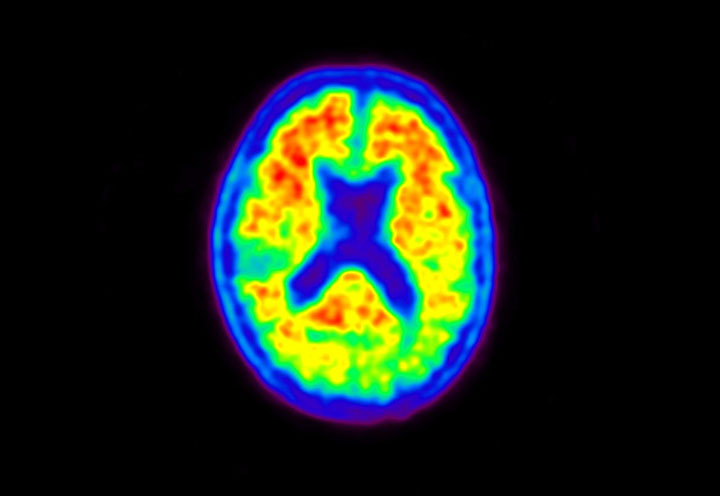

Head / Case5 : Amyloid

Axial

Courtesy : Kindai University Hospital

- Imaging protocol

- Injected dose: 4.27 MBq/kg, 18F-Flutemetamol

- Uptake time: 99 minutes

- Scan time: 20 minutes